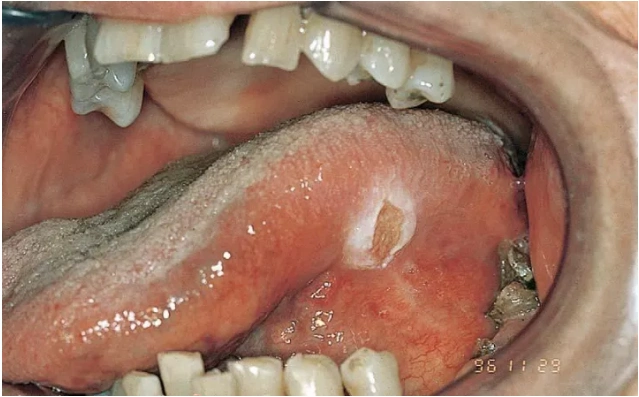

舌头溃疡长期不好,警惕舌! - 好大夫在线